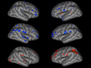

Discovery of a faulty connection between genes in mice with Rett syndrome has brought the possibility of effective therapies a step closer for this rare but devastating disorder in humans. The faulty link is believed to cause a gene called Irak1 to over-produce a protein, stunting the growth of brain cells called callosal projection neurons (CPNs) – pictured, stained green, in a section of a mouse cerebral cortex. When scientists reduced the activity of Irak1 in mice with Rett syndrome, levels of the protein fell back to normal, the CPNs developed properly and the mice had fewer symptoms. In humans, Rett syndrome often causes severe disability and loss of speech in girls from an early age. It’s rare in boys because male foetuses don’t often survive to birth.